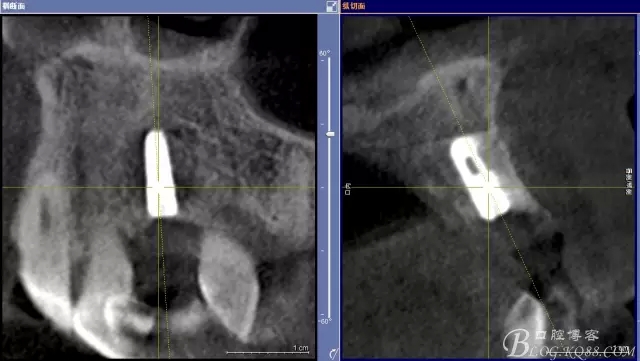

圖1.術(shù)前的CBCT檢查:22缺失。

圖2.CBCT的三維成像及縱剖面、水平面影像